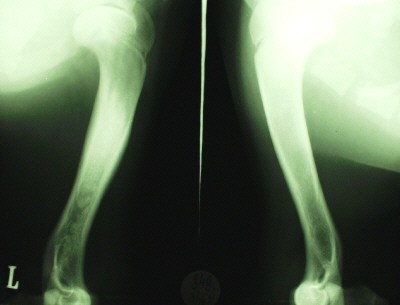

Röntgenbild: linke Vordergliedmaße

Weißer Schäfer - männlich - 10 Monate

Panostitis im Ober- und Unterarm

Deutscher Schäfer - weiblich - 7,5 Monate

hochgradige Panostitis im Oberarm